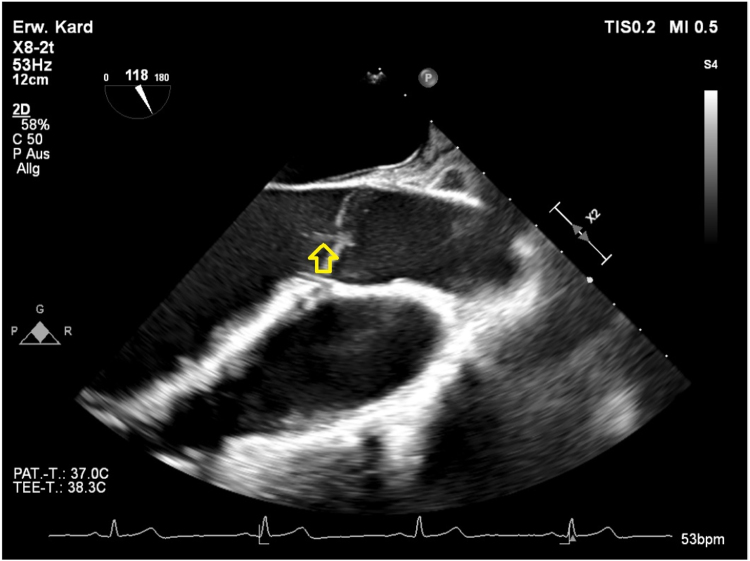

Case report: A 41-years-old male patient with sonographically confirmed, culture-negative endocarditis accompanied by repeated fever episodes received 4g ceftriaxone per day next to ampicillin and gentamicin as an element of his antibiotic therapy. At day 4 of treatment, signs of gall bladder sludge and biliary pseudolithiasis were first seen in sonography. At day 17, abdominal pain over 30 min and increased liver and pancreatic enzymes pointed towards temporal duct obstruction as a complication and ceftriaxone therapy had to be preterm cancelled. A sonographic work-up of the stepwise improvement of the sonographic findings after the end of the ceftriaxone therapy is provided, a reemergence of endocarditis was not observed.